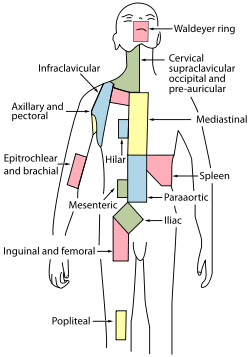

Regional lymph tissue. (Cervical near top, in green.)⋅ | |

Cervical lymph nodes are lymph nodes found in the neck. Of the 800 lymph nodes in the human body, 300 are in the neck.[1] Cervical lymph nodes are subject to a number of different pathological conditions including tumours, infection and inflammation.[2]

There are approximately 300 lymph nodes in the neck, and they can be classified in many different ways.[1]